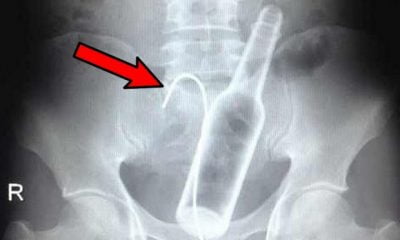

Υπάρχουν πολλά είδη τραυματισμών που μπορεί να γίνουν από τη μια στιγμή στην άλλη και αποτελούν ένα φυσιολογικό κομμάτι της ζωής μας. Αυτό που μερικές φορές...